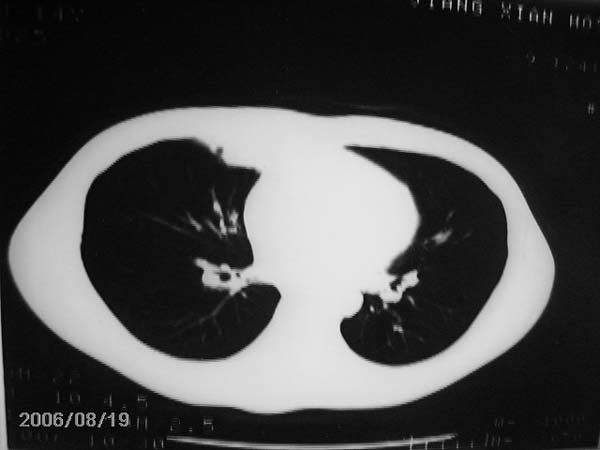

男,13岁,发烧半月,干咳无痰,正规使用抗生素半月,现在仍是午后低烧!!!未做痰检

结合临床考虑:右肺中叶结核可能性大.

右肺中叶结核可能性大

右肺结核,右肺中叶不张

右侧肺门淋巴结好象有增大,会不会是个原发综合症合并感染

右中肺呈大片状密度欠均匀影,内见含气支气管.

结合病史,考虑:右中肺大叶性肺炎(吸收期).

右肺中叶大片状密度增高影,内密度不均匀,右肺门处增大,应该是淋巴结肿大,结合临床首先考虑原发性肺结合可能性大,不排除合并感染可能,建议治疗后复查.